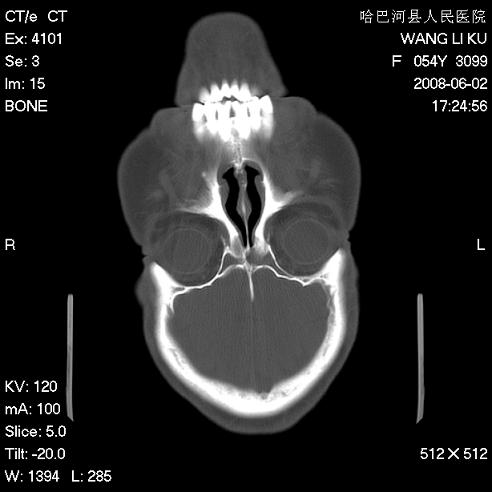

标题: CT13803:反复性鼻塞、流涕一年余 [打印本页]

标题: CT13803:反复性鼻塞、流涕一年余

副鼻窦炎,右上额窦积脓。左眼肌锥内见致密影,视神經受压

1.全组副鼻窦炎2.双侧上颌窦积液

全组副鼻窦炎 肌锥内高密度灶。建议进一步检察检查

1、全组副鼻窦炎。

2、左眼眶肌锥内病变,小血管瘤?建议增强。

1)全副鼻窦炎(左侧上颌窦黏膜下囊肿或息肉)。2)左眼眶肌锥内不规则小结节状软组织密度影;考虑为小血管瘤可能。建议行ct增强扫描检查。

全组副鼻窦炎,左侧肌锥内不规则形软组织肿块影,与眼外肌密度相当,左侧视神经受压,肿块与视神经及眼外肌分界清晰,眼外肌无增粗,眶壁无破坏,球后脂肪间隙不模糊,考虑良性改变,小血管瘤或神经源性肿瘤可能,建议增强扫描。

谢谢,增强扫描做了,眶内病灶与海绵窦同步明显强化,血管瘤